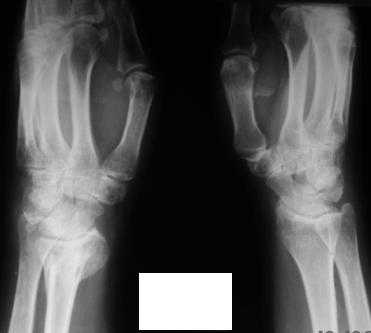

Уважаемые коллеги! Обратилась женщина, 55 лет. Травма 3 месяца назад, лечилась по месту жительства (Рис.1). Косорукость, боли, ограничение движений.

Досняли - рис.2-6. Хотелось-бы услышать мнения об объеме операции. С уважением, Юрий Алексеевич Булахтинглавный травматолог Камчатского Военно-морского госпиталя

u pazientki po nauchnomu ulna abutment/impingment syndrome posle posttraumaticheskogo ukorochenia radiusa

na rengene znachitelnoe ukorochenie radiusa, sustavnaia poverchnost naklonena dorsalno chresmerno , chetko vidno nekongruentnost DRUJ - distalnogo radioulnarnogo sustava ,ulna prosto vtikaetsia v triquetrum .

ia bi vibral vosstanovlenie dlinni i anatomichescogo voliarnogo naklona radiusa , osteotomia cherez dorsalnii podxod , kortikocanzeloznii graft iz taza , rigidnaia fixacia (luchse 2 mini plate LCP 2.o,) esli net to kirshneri no togda dolgo bes dvizeniia v gipse .izbegaite naruznix fixatorov tolko v ochen krainix sluchaiax .

esli polnostiu ne udaetsia udlinnit togda odnovremenno ukorotite ulnu .

Да, действительно, в наличии так называемый посттравматический ulnar impaction syndrome. Есть несколько вариантов лечения этой патологии-данного случая. Вполне можно выбрать вариант и предложенной выше тактики. А кто-то даже после остеотомии лучевой кости наложит аппарат внешней фиксации и одновременно устранит дорсальную ангуляцию и удлинит лучевую кость. Можно предусмотреть и другие варианты. Если не очень расстраивает дорсальная ангуляция, то при отсутствии артроза в области дистального радиоульнарного сочленения ( а пока такого, по-видимому, нет)и нестабильности этого сустава можно просто укоротить локтевую кость. Причем возможно сделать поперечную остеотомию ( если есть ладонный или тыльный подвывих головки локтевой кости, то можно сделать еще и клиновидную остеотомию по ладони или по тылу), либо выполнить косую остеотомию ( при подвывихе головки даже клин в этом случае не надо делать). Если есть артроз, нестабильность, то нужно рассматривать другие варианты - Дарраха в модификациях, Сауве-Капанджи, артропластику(?).